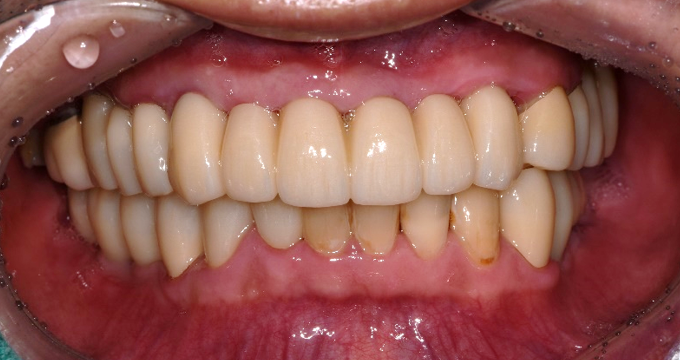

치료 후

무너졌던 교합고경이 회복되어 치료 전 합죽이처럼 보이던 하안모가 연령에 맞는 정상적인 외형으로 복구되었습니다.